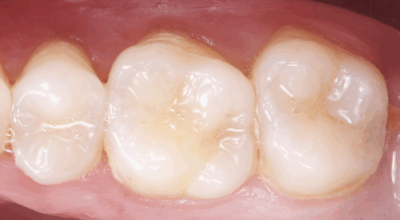

Cas clinique d’une 17 (2e molaire en haut à droite)

Coiffage pulpaire indirect : 96,4% de taux de succès